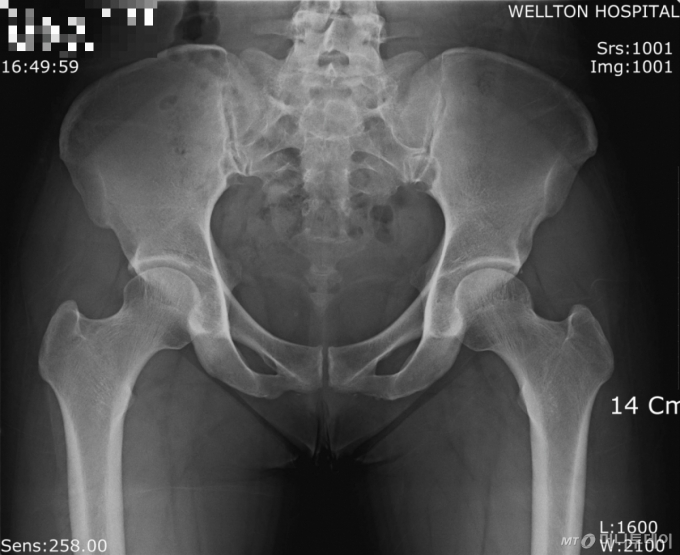

정상인의 고관절 엑스레이 사진. |

고관절 골절은 골밀도와 근력이 떨어진 어르신이 넘어졌을 때 잘 발생하는 중증 질환이다. 고령자의 고관절 골절은 단순 골절과 달리, 조기 수술과 집중 치료가 예후에 큰 영향을 미친다. 고관절 골절 후 수술받은 환자가 누워지내다가 1년 내 사망할 확률은 14.7%, 2년 내 사망률은 24.3%로 집계됐다. 그렇다고 고관절 골절 후 아예 방치하는 건 더 위험하다. 방치한 사람의 1년 내 사망률이 25%, 2년 내 사망률은 70%에 달해서다.

고관절 골절 수술의 골든타임은 24시간 이내이지만, 늦어도 48시간을 넘기지 말아야 한다. 이보다 수술이 늦어지면 폐렴, 욕창, 심혈관계 합병증 같은 2차 합병증이 발생할 위험이 커진다.